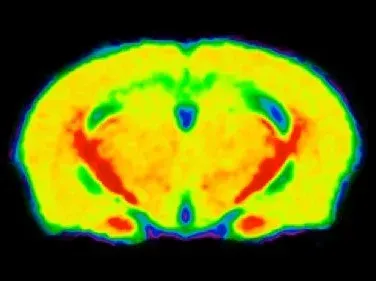

MTR map of a cuprizone mouse brain showing low (green) signal in the corpus callosum.

In vivo MRI Measures

Multi-modality brain imaging biomarkers are widely used in clinical trials of multiple sclerosis. MRI-derived measures of lesion volumes, gadolinium enhancement, lesion biophysical characteristics, and brain atrophy are effective biomarkers of disease progression and response to therapy.

Using whole-brain, high-resolution, anatomical MRI acquisition paired with advanced fully-automated image processing & analysis, we have shown:

- Reproducible magnetization transfer ratio (MTR) measures in the cuprizone model of MS, allowing for longitudinal monitoring of demyelination & remyelination